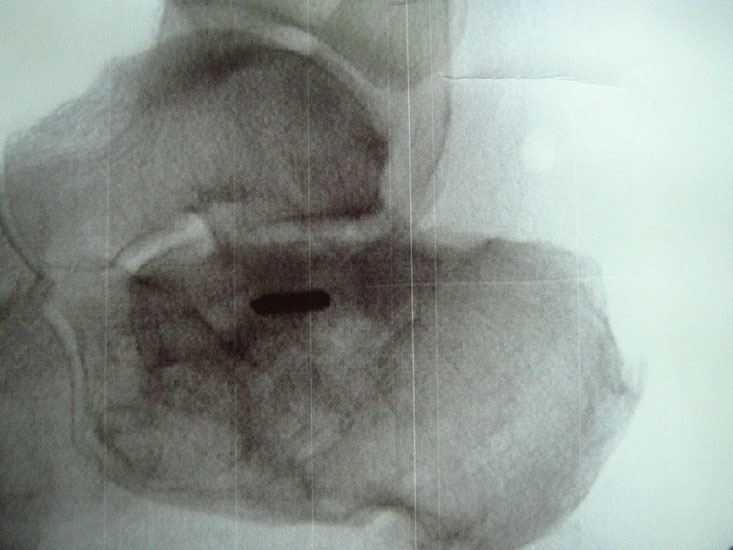

Abbildung Nr. 17 und 18, Video Nr. 3

Das arthroskopische Verfahren eignet sich auch zur Resektion multipler Ossikel (*) und Osteophyten (O). Hier ist der intraoperative Einsatz eines Bildverstärkers unabdingbar, um keine Knochenfragmente im Weichteilgewebe zu übersehen. Zur Osteophytenresektion können problemlos kleine Flachmeißel über die Arthroskopiezugänge verwendet werden (rechte Seite, m= medial, l= lateral, FHL=Flexor hallucis longus-Sehne).

Abbildung Nr. 19-22

Knochenresektat sowie präoperatives CT (Sagittal- und Transversalebene) und intraoperative Bildwandlerkontrolle im seitlichen Strahlengang nach arthroskopischer Entfernung multipler Ossikel am dorsalen OSG/USG.

Abbildung Nr. 23 und 24, Video Nr. 4

Große osteophytäre Anbauten, welche die FHL-Sehne vollständig ummauern, sind ebenfalls sehr gut in der beschriebenen Technik adressierbar. Präoperatives CT und intraoperative Bildwandlerkontrolle im seitlichen Strahlengang (linke Seite).